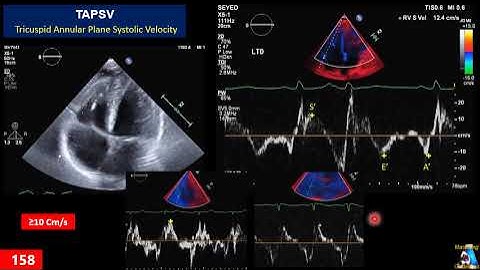

RIGHT VENTRICULAR SERIES PART 2 - RV FUNCTION ASSESSMENT METHODS